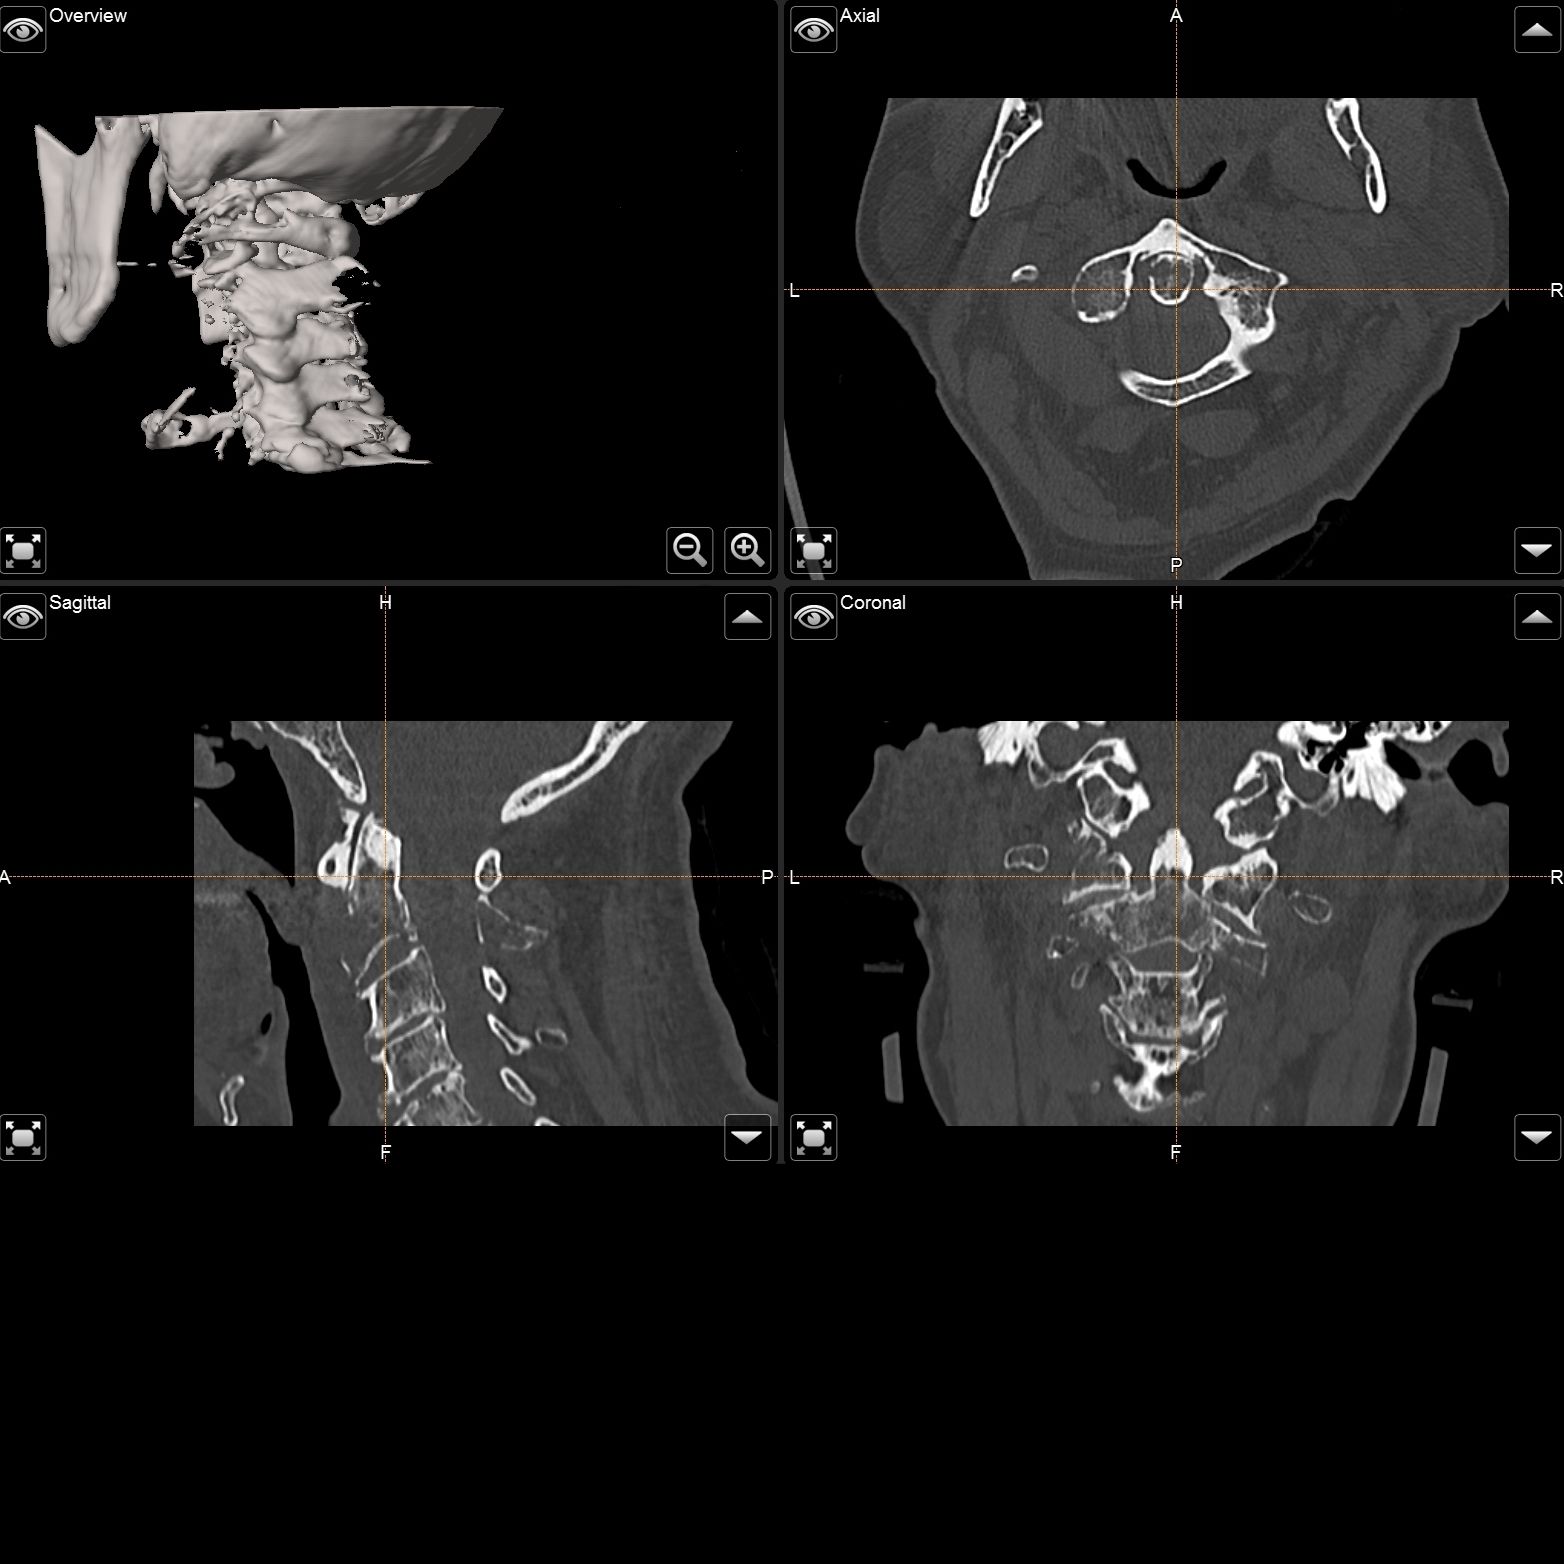

Die Universitätsklinik Tübingen verfügt über hochmoderne mobile Bildgebungssysteme, darunter der robotisch geführte digitale Volumentomograph Loop-X der Firma Brainlab sowie ein mobiler 3D-C-Bogen der Firma Ziehm. Diese fortschrittlichen Systeme ermöglichen intraoperativ eine präzise 3D-Rekonstruktion des Kopfes oder der Wirbelsäule. Für die Kopf- und Wirbelsäulenchirurgie kann mithilfe dieser Technologien ein Navigationsdatensatz erstellt werden, der eine hochpräzise Navigation gewährleistet. So können beispielsweise Schrauben in der Wirbelsäule exakt platziert und kontrolliert oder Trajektorien für Zugangswege und Probenentnahmen im Kopf definiert werden.